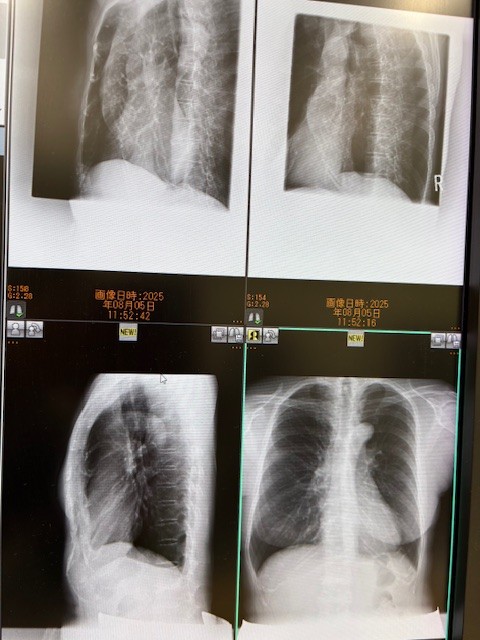

一応心配なのでレントゲンを撮りに行きました。

大丈夫でした。佐藤直子